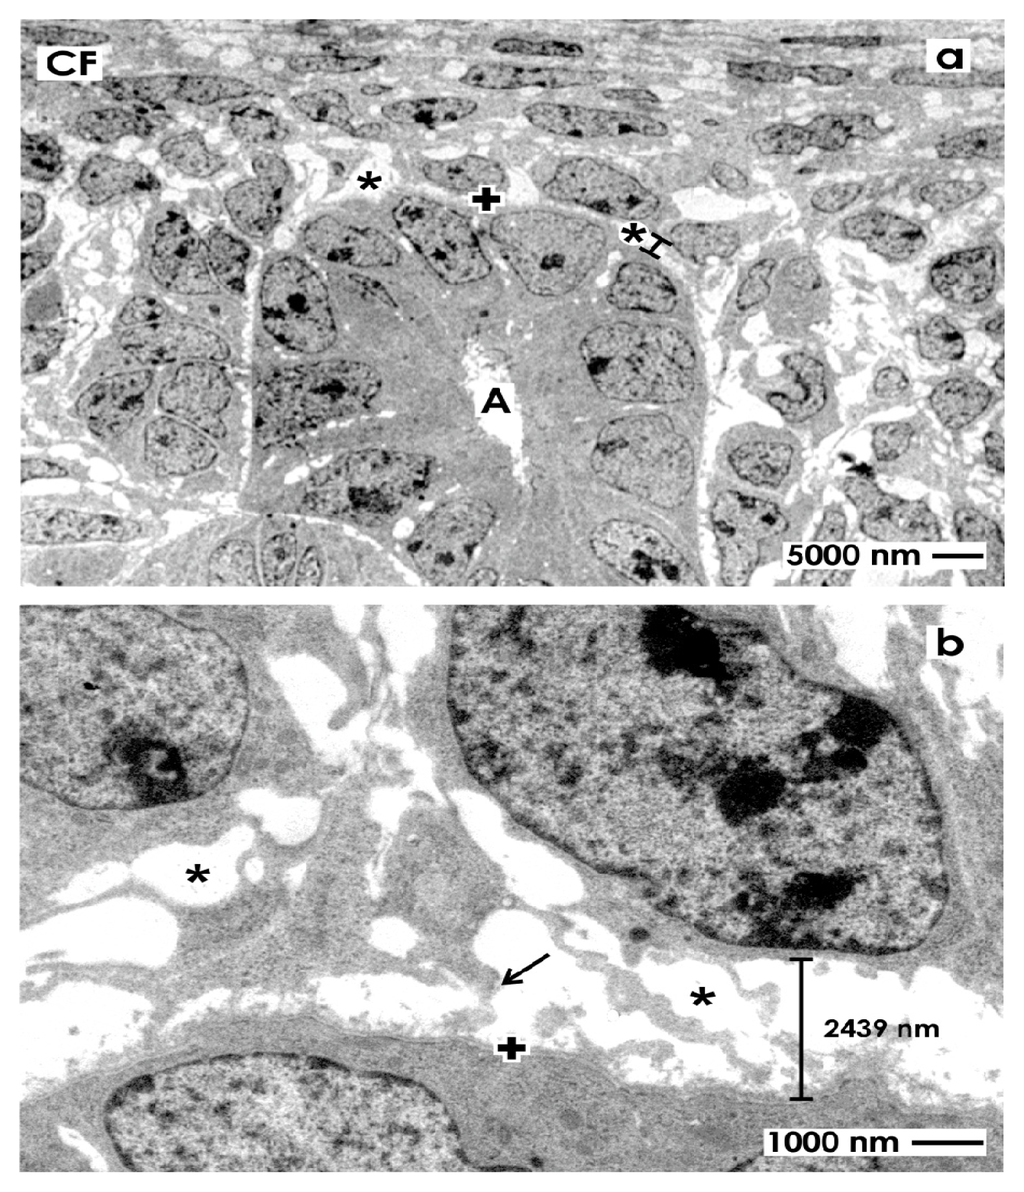

2.3. Electron Microscopical View to the Renal Stem/Progenitor Cell Niche

2.3.1. Traditional Fixation with Glutaraldehyde (GA)